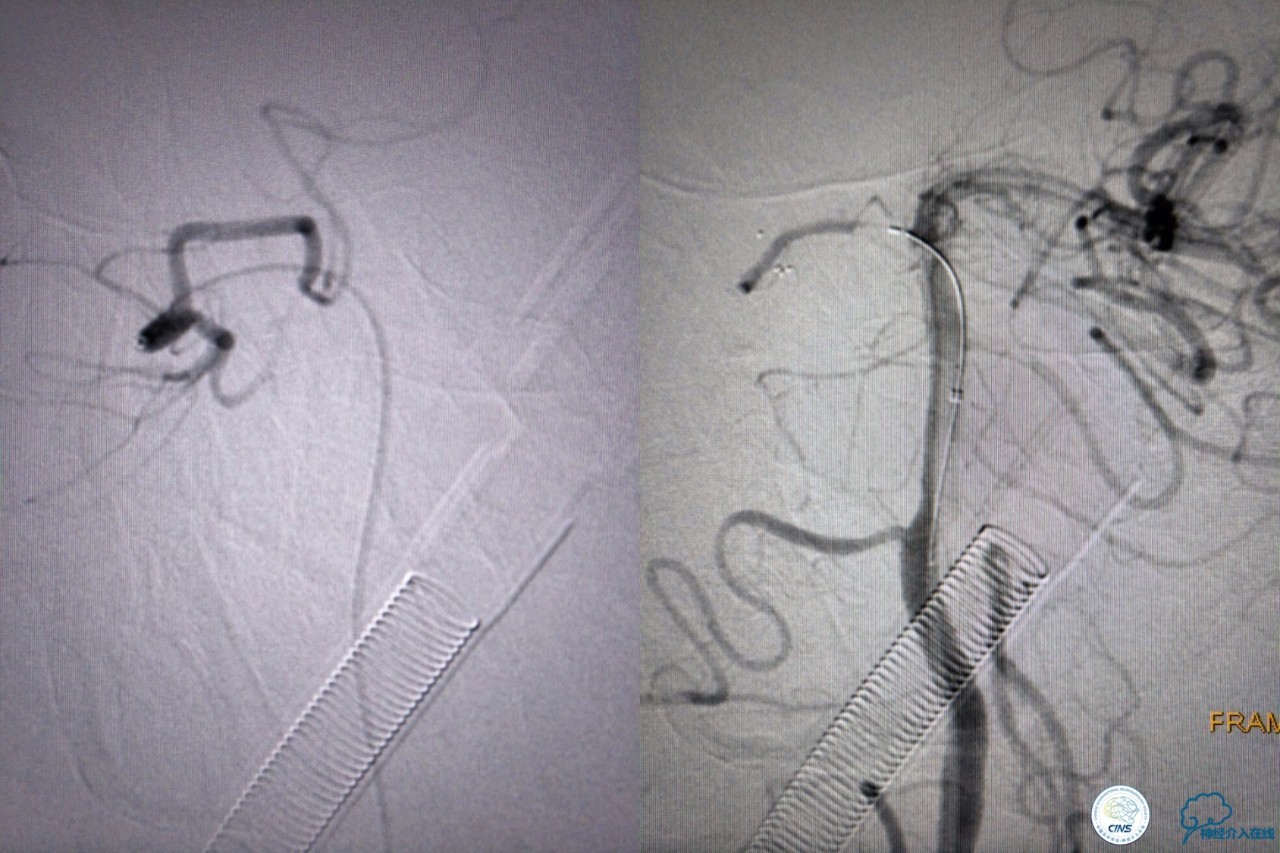

第三次取栓后,左侧大脑后动脉开通,但是栓子再次栓塞右侧大脑后动脉,血栓在基地动脉顶端来回左右摆动,下一次,怎办?血栓负荷太多,可以使用solumbar技术,可以没有颅内导管,没办法,换用更大的支架6-20mm,但费用增加不少,与家属沟通后同意使用,第四次取栓:

血栓负荷还是很大,左侧大脑后再通,但右侧大脑后又闭塞,只能第五次取栓,支架放到右侧大脑后动脉更远。

好大的血栓,支架释放后,血管无复流,拉一把!